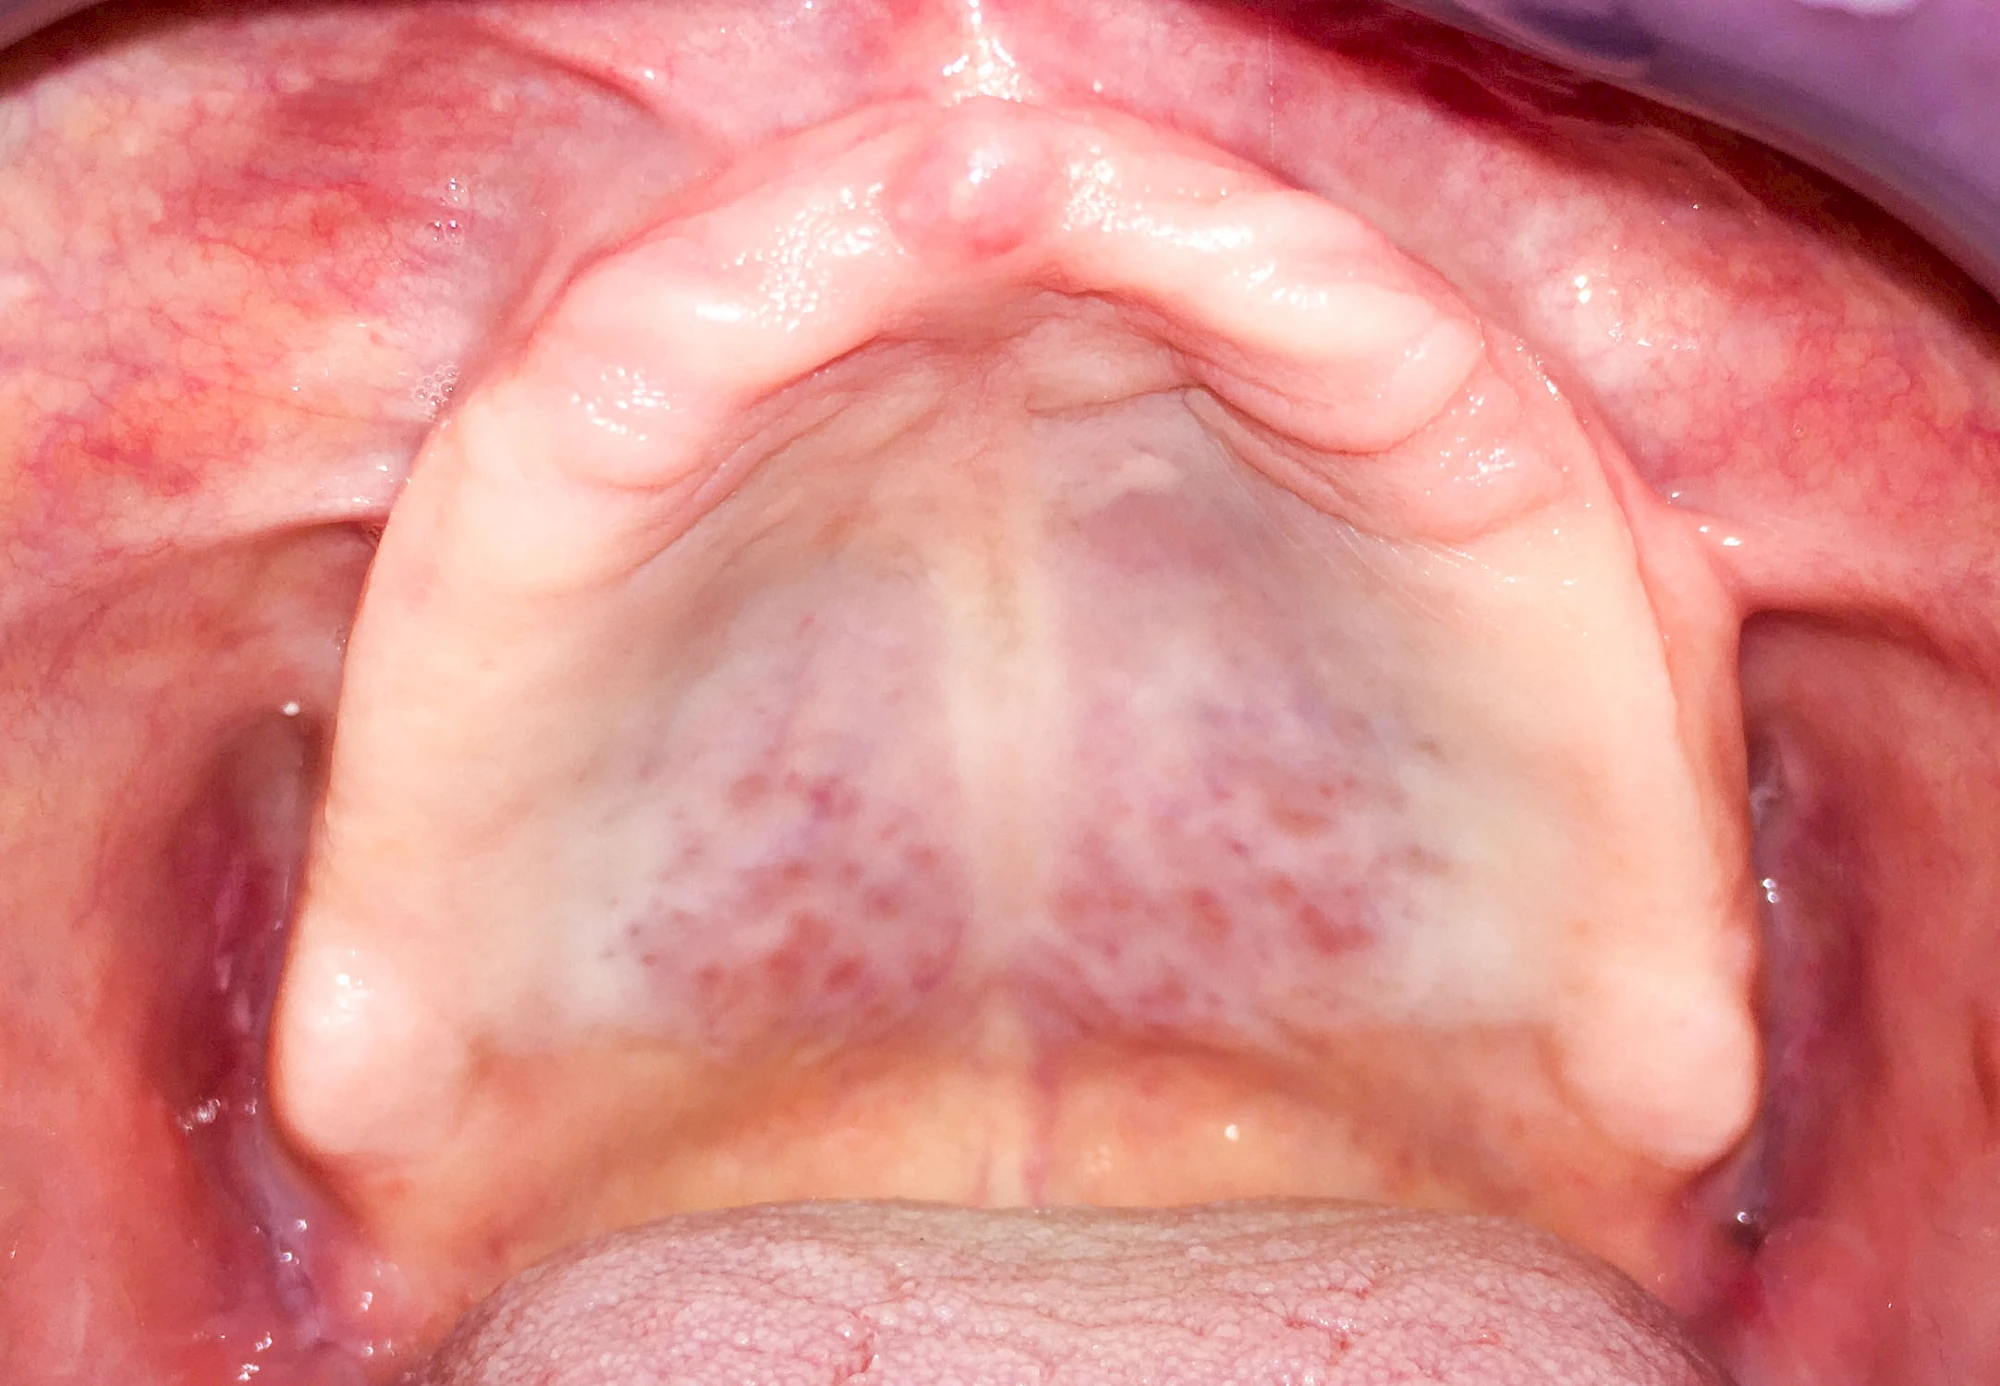

Lippen-Kiefer-Gaumenspalten (LKG-Spalte) sind angeborene Fehlbildungen im Mund-Kiefer-Gesichtsbereich. Die Gewebestrukturen im Bereich des Oberkiefers sind im Zuge der Entwicklungen bis zur Geburt nicht zusammengewachsen. Diese Fehlbildung zählt zu den häufigsten Fehlbildungen des Menschen, von 500 Neugeborenen ist eines betroffen. Die Fehlbildungen können sich auf Lippe, Gaumen und Kiefer allein beschränken, treten häufig aber kombiniert und in seltenen Fällen sogar beidseits auf.